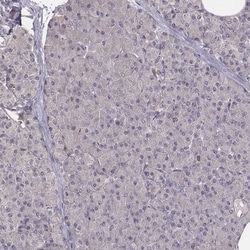

Invitrogen™ PILRA Polyclonal Antibody

Supplier: Invitrogen™ PA566000

| Immunohistochemistry (Paraffin) | |